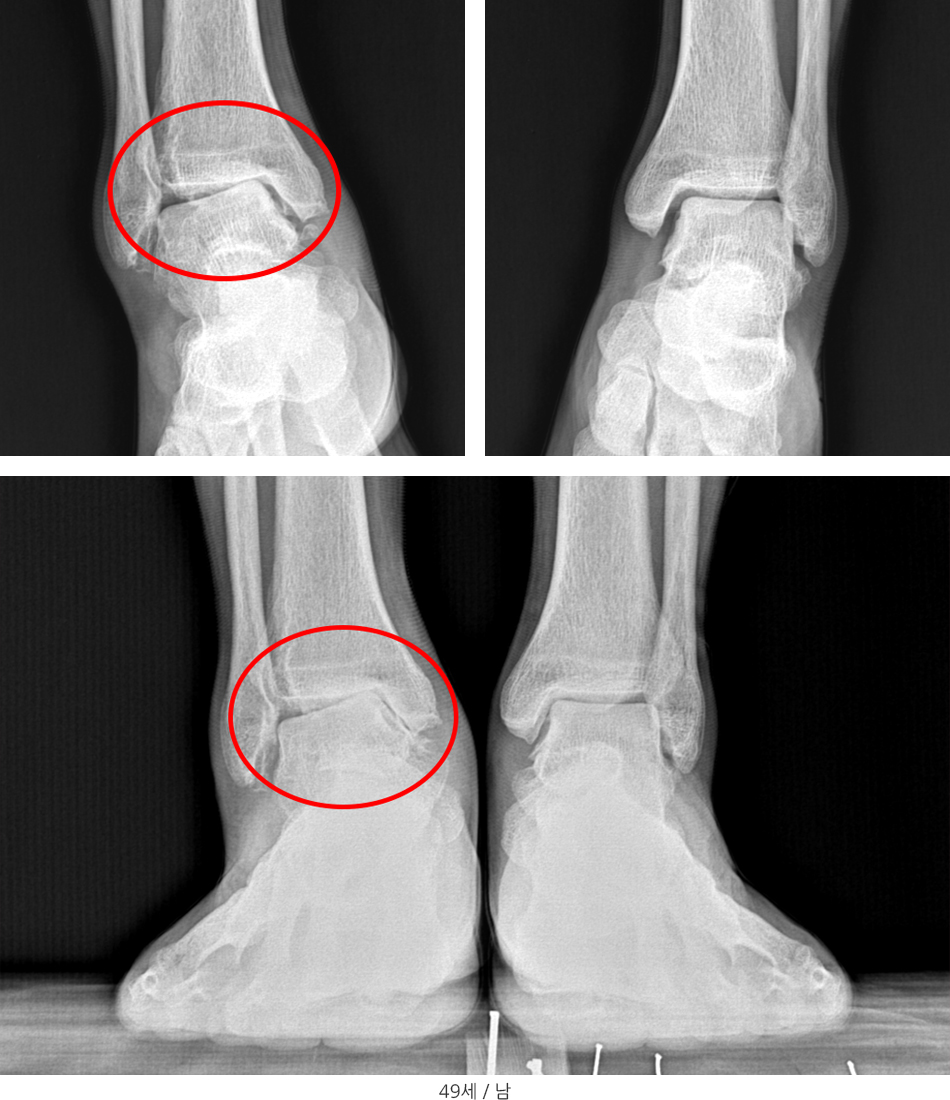

※ 바깥쪽(화살표) 인대가 파열되면 불안정으로 발목안쪽을 쳐대서 안쪽부위의 관절염이 진행되는 상황이 올 수 있으므로 발목인대파열은 초기 수상 시 정확한 진단 및 치료가 매우 중요합니다.